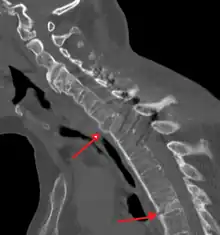

The earliest changes demonstrable by plain x–ray shows erosions and sclerosis in sacroiliac joints. Progression of the erosions leads to widening of the joint space and bony sclerosis. X-ray spine can reveal squaring of vertebrae with bony spur formation called syndesmophyte. This causes the bamboo spine appearance. A drawback of X-ray diagnosis is the signs and symptoms of AS have usually been established as long as 7–10 years prior to X-ray-evident changes occurring on a plain film X-ray, which means a delay of as long as 10 years before adequate therapies can be introduced.[21]

Lateral X-ray of the mid back in ankylosing spondylitis -

Lateral X-ray of the neck in ankylosing spondylitisImaging -

X-ray showing bamboo spine in a person with ankylosing spondylitis -

CT scan showing bamboo spine in ankylosing spondylitis -